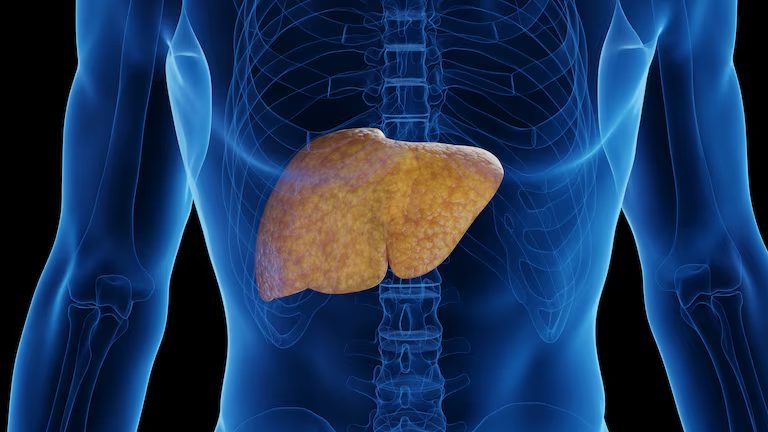

Silencioso e cada vez mais comum, o excesso de gordura no fígado, tecnicamente chamado de esteatose hepática metabólica (antigamente conhecido por esteatose hepática não alcoólica), já atinge cerca de um terço da população mundial – e a tendência é continuar aumentando. Ter gordura no fígado significa que as células hepáticas estão acumulando lipídios, algo que pode acontecer em qualquer pessoa, mesmo magra, mas é mais comum entre quem tem sobrepeso, obesidade ou diabetes.

“Esse acúmulo de gordura se torna uma doença quando ultrapassa 5% das células do fígado. Acima disso o órgão já está sobrecarregado e pode evoluir com inflamação, fibrose e, nos casos mais graves, cirrose e câncer hepático, caso o problema não seja diagnosticado e tratado adequadamente”, explica a hepatologista Natália Trevizoli, do Hospital Sírio-Libanês, em Brasília.

O aumento da esteatose hepática é impulsionado por dietas com produtos ultraprocessados, sedentarismo, sono irregular e estresse. Por isso, especialistas chamam a condição de “epidemia silenciosa”. “Muitas pessoas descobrem por acaso, em exames de rotina, porque a doença pode evoluir por anos sem causar sintomas”, diz Natália.

Mas o que significa, afinal, “emagrecer o fígado”? Segundo os especialistas, a expressão traduz o esforço de reduzir a gordura acumulada nesse órgão, algo que depende diretamente de mudanças no estilo de vida.

“Trata-se de reduzir a gordura corporal como um todo, especialmente a gordura visceral, que é aquela que se acumula na região abdominal. Esse tipo de gordura é mais perigoso, pois libera substâncias inflamatórias que agravam o dano hepático e aumentam o risco cardiovascular”, diz o hepatologista Luís Edmundo Fonseca, do Centro Especializado em Aparelho Digestivo do Hospital Alemão Oswaldo Cruz.

Estudos mostram que perder entre 7% e 10% do peso corporal já pode normalizar enzimas e melhorar a estrutura do fígado, por isso os médicos reforçam que perder peso é o principal caminho, mas a qualidade dessa perda também faz diferença. “Qualquer perda já traz benefícios. Mesmo 5% de perda de peso pode reduzir a gordura hepática e melhorar os exames”, pontua Fonseca.